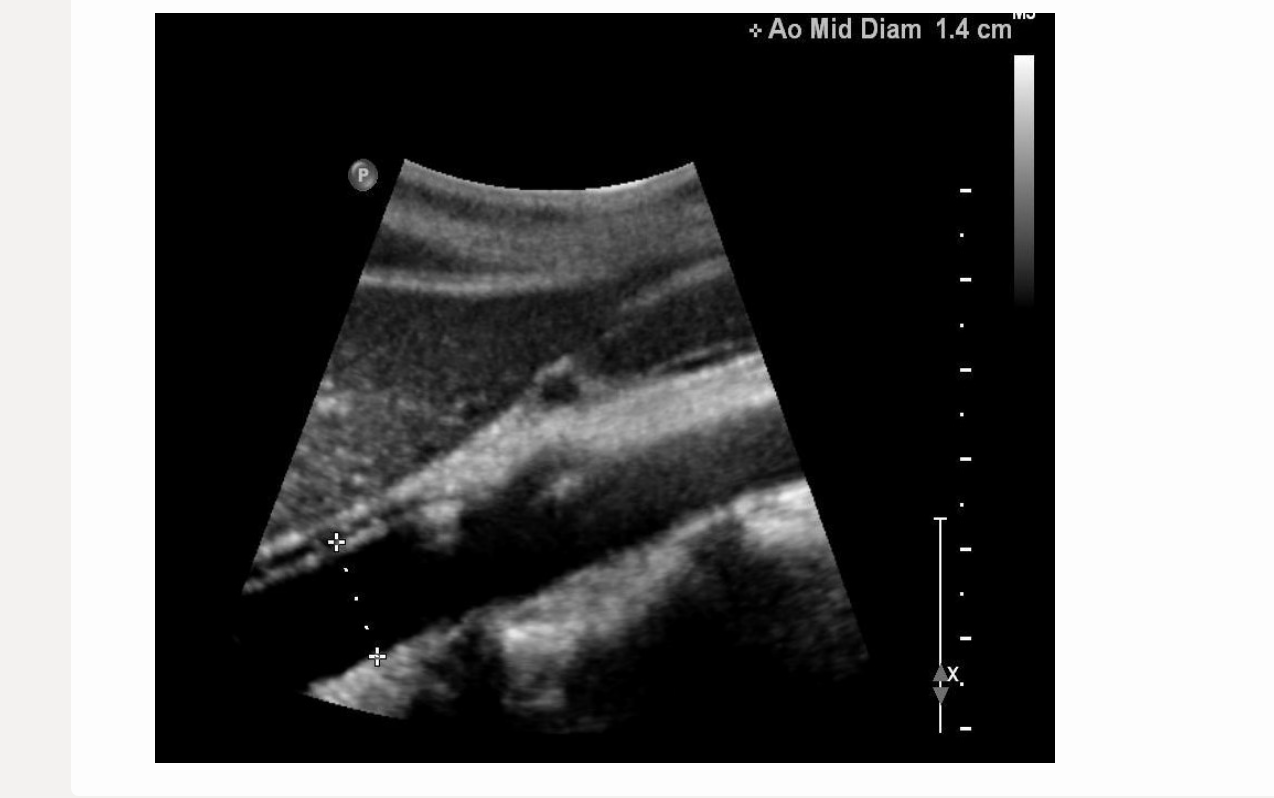

which describes a normal renal artery waveform

.

a) low resistance w/increased diastolic flow

b) increased diastolic flow reversal

c) biphasic w/mild diastolic flow reversal

d) pulsus alternans [methodical variation in peak vel on every other beat]

a. low resistance w/increased diastolic flow